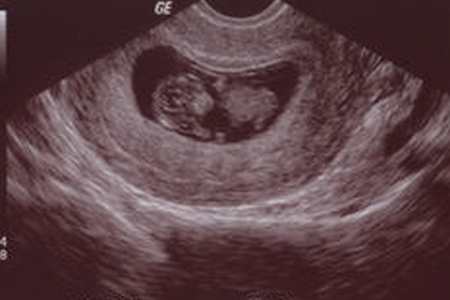

在怀孕早期要注意胎心和胎牙是否出现,胎心和胎芽出现的时间既与怀孕时间有关系,也与孕囊的大小有关系。有些女性月经比较准,而且周期为30天左右,这种情况下可以根据怀孕时间来判断是否存在胚胎停育。

而有些女性月经不规律或者忘记了大体是什么时间段受孕的,对于这种情况应该根据孕囊的大小来判断孕囊的生长发育情况。正常情况下,孕囊直径在三厘米以内就应该出现胎心和胎芽。

如果孕囊的直径超过三厘米以上,仍然看不到胎心和胎芽,这种情况就可以确诊为胚胎停育,可以直接流产。因为按照孕囊的正常发育规律,超过三厘米以上就肯定不会再出现胎心和胎芽了,因为此时怀孕时间大概也就是9~10周左右,已经达到了胚胎停育的诊断标准。